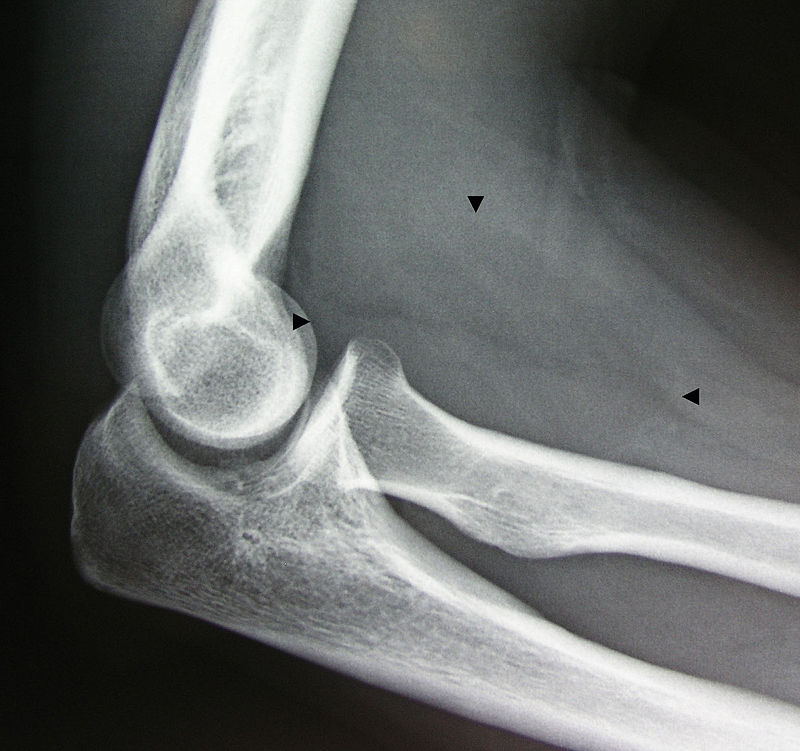

A lipoma is a benign tumor composed of adipose tissue that typically develops just beneath the skin.

Lipomas may be treated by surgical excision.